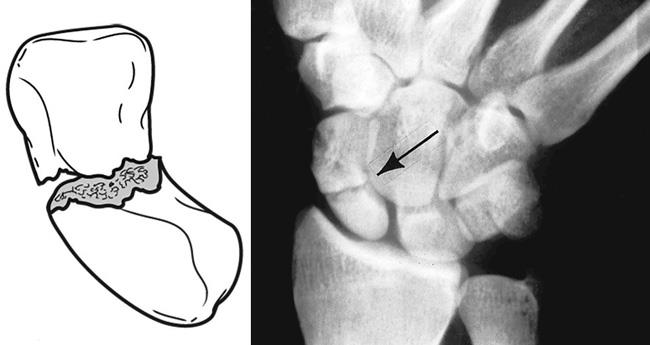

골절은 대게 Waist 라고 불리는 가운데 부분에서 진행되는 경우가 많으며(2), 10%는 근위부(1), 나머지 극소수(3)에서는 원위부에서 이러한 골절이 이러나게 됩니다.

분류는 Herbert Classification 을 통해 분류할 수 있습니다.

A부터 D 타입으로 나눌 수 가 있는데

A의 경우 급성 안정골절, B의 경우 급성 불안전 골절, C의 경우 지연유합, D의 경우 불유합 으로 나뉠 수 있습니다.

불안정한 급성골절인 B의 경우 수술적 치료가 필요한 경우가 많기 때문에 주의깊게 보아야 합니다.